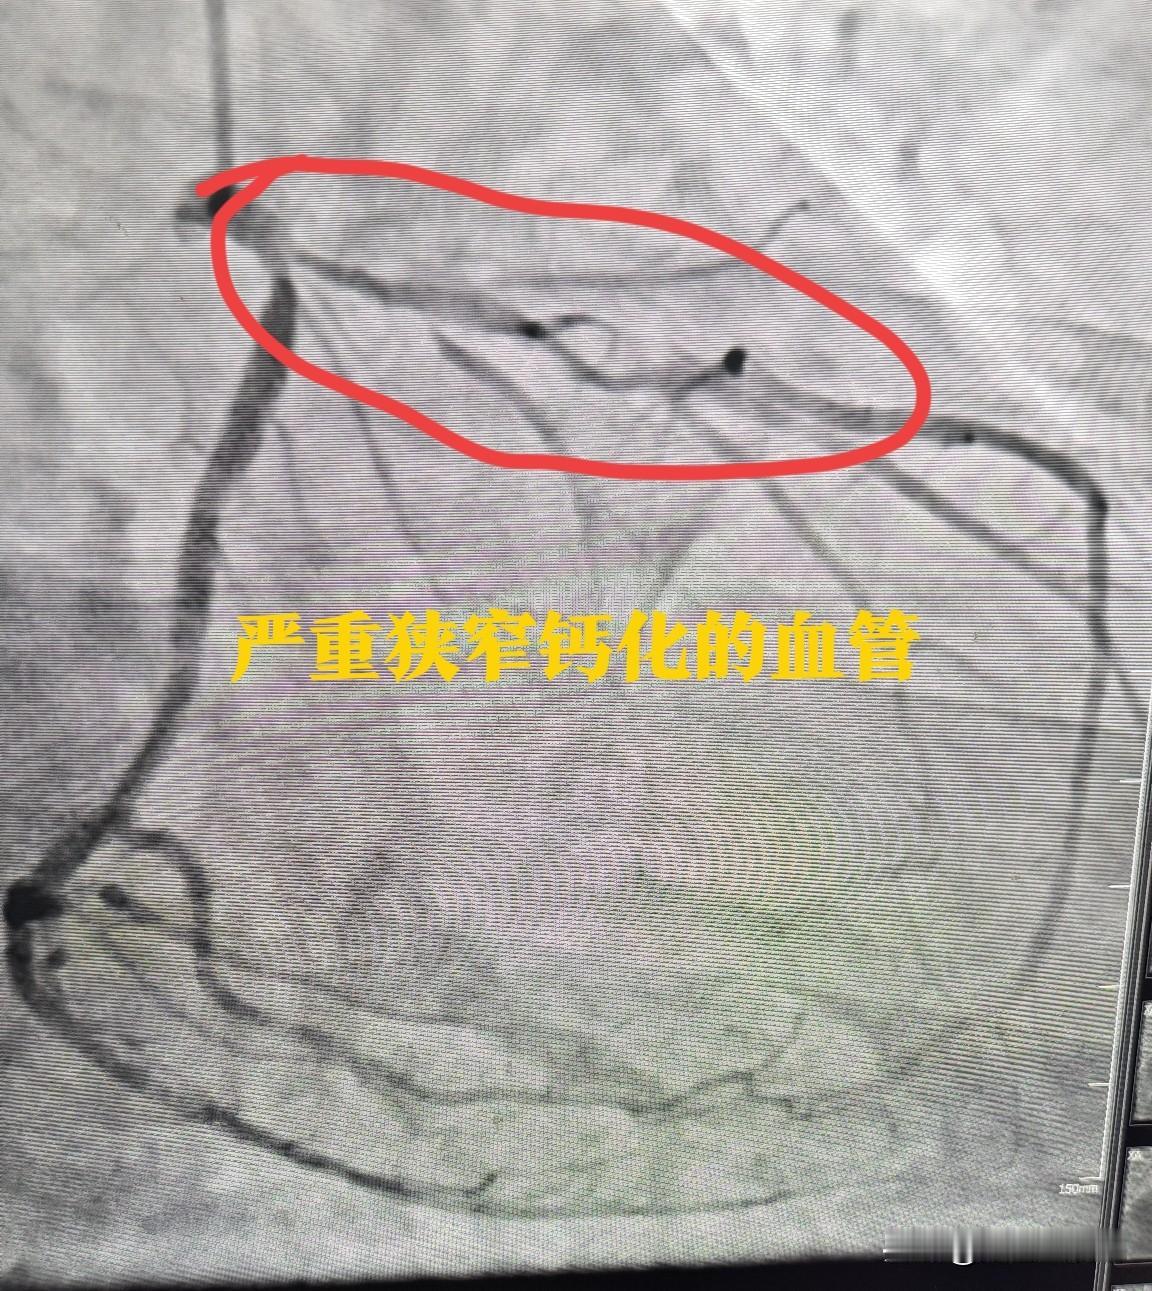

给83岁老爹爹做冠脉旋磨手术是什么体验?就是太惊险了。惊险的感觉。83岁男性患者

2025-11-24 23:26